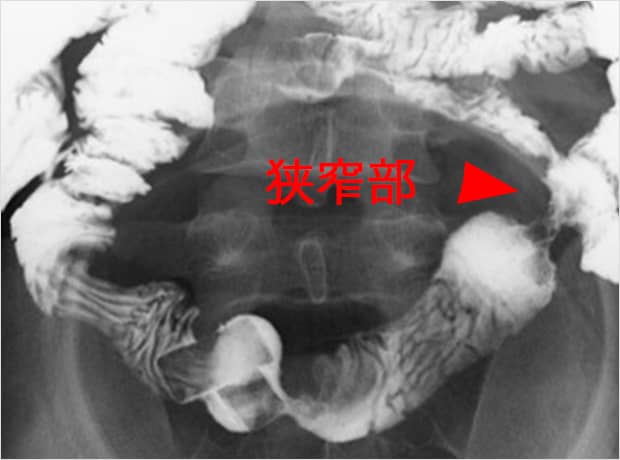

[X線造影検査]

クローン病の狭窄病変のX線です.